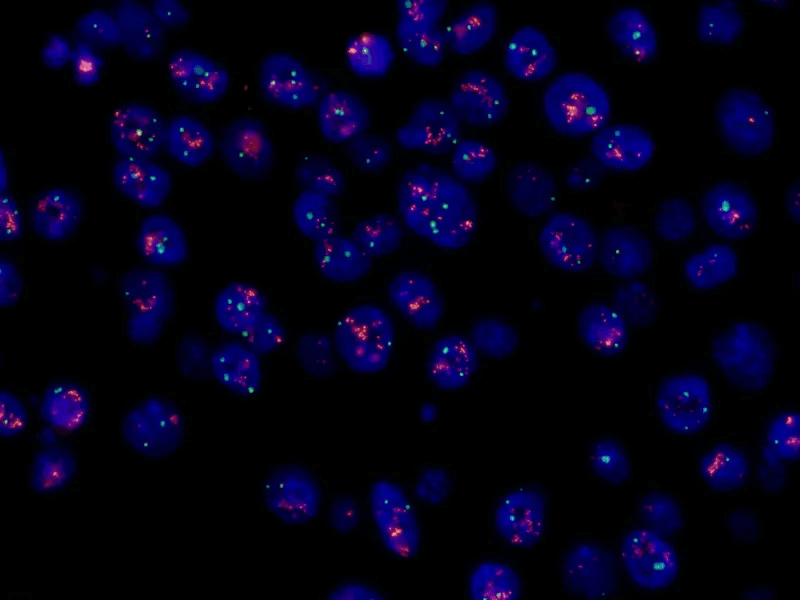

3. ÔÎģÉšâësŊģŖ¨FISHŖŠŖēģųŌōŽŗŖĩēסÛÆ÷”

MF43-NÉšâī@ÎĸįR´îÅäMC50-SĪāCŖŦŋÉžĢʲļ×ŊÉšâËĶĩÄDNAĖŊáĐÅĖŖŦ¸ßЧzyČéĪŲ°ŠĄĸmîi°ŠĩČŧ˛˛ĄÖĐĩÄģųŌōUÔöģōȹʧŖŦÖúÁĻĐÔģ¯Ô\¯ĄŖ

MF43-N+MC50-S´îÅäËIJ¨ļΚâÔ´ÅÄzĩÄFISHDĪņ